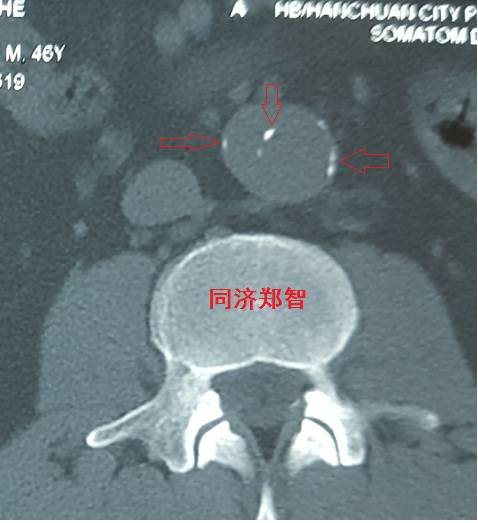

病例十

腹主动脉平扫CT提示正常外周一圈的钙化影中有内移的钙化影(红色箭头所示),CTA 证实为腹主动脉夹层